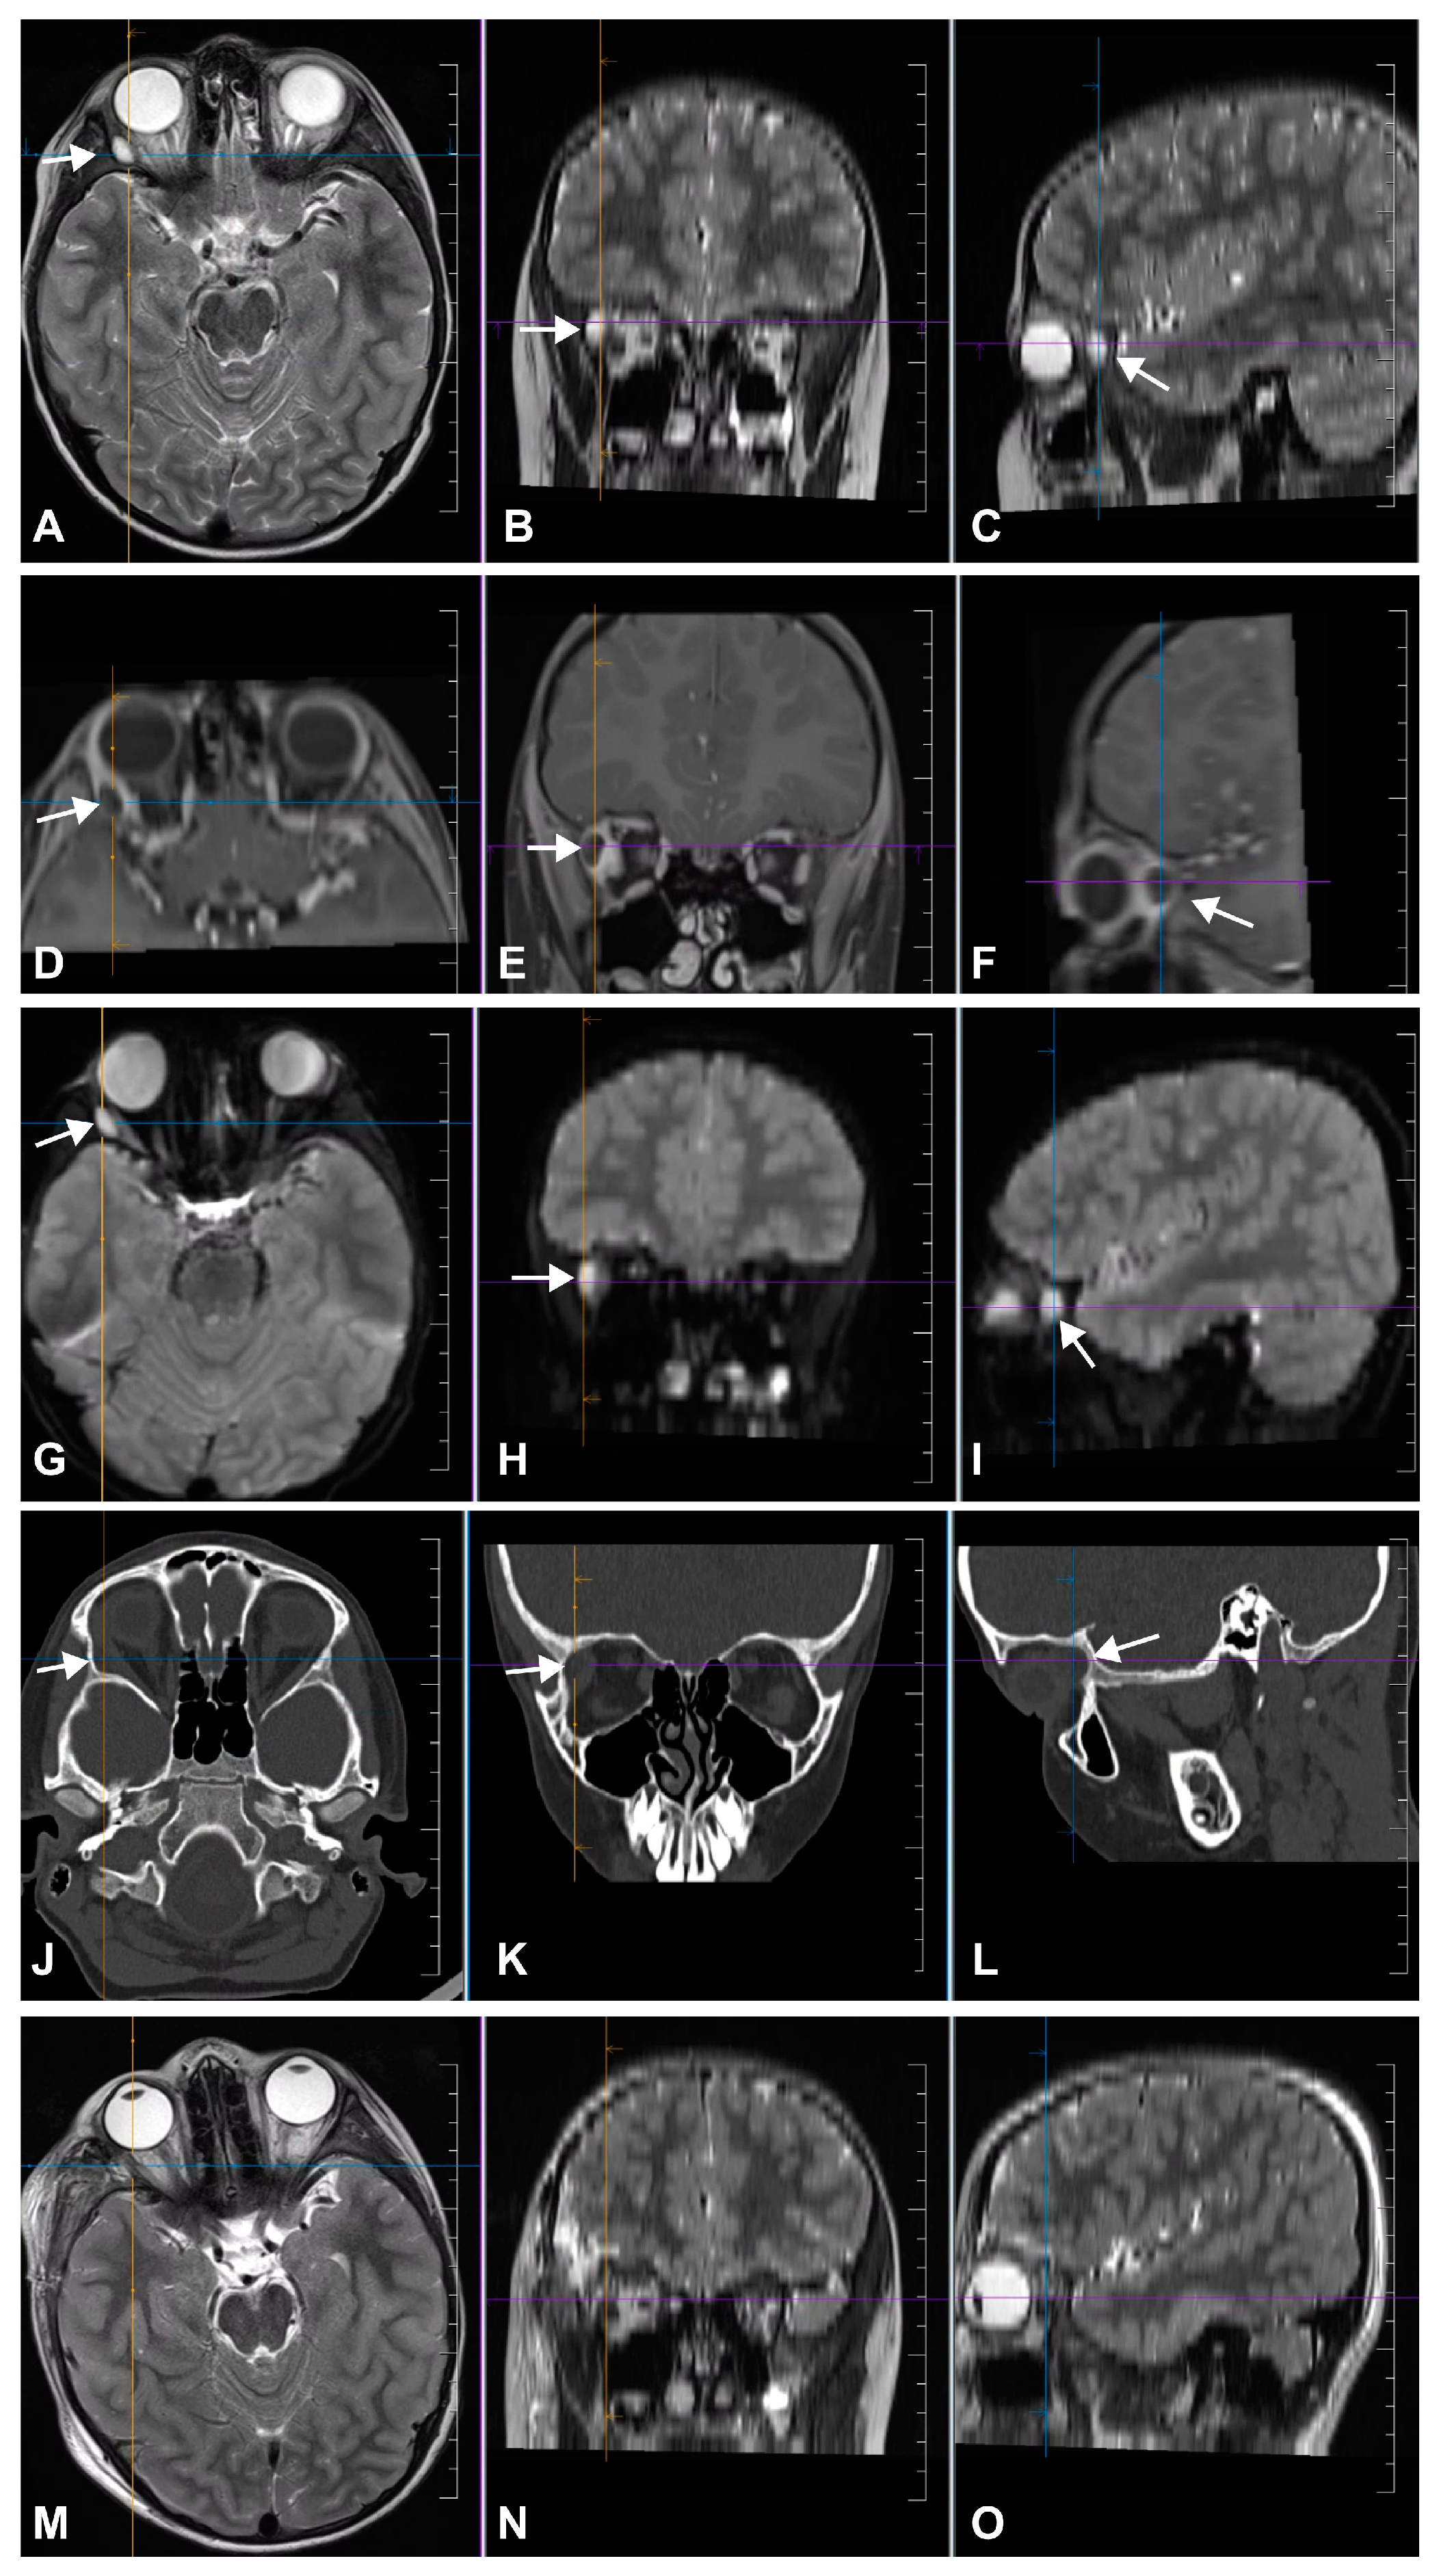

MRI revealed a 7 mm diameter residual epidermoid cyst located posterior to the initial lesion in the superolateral extraconal area that extended to the apex of the orbit (Figure 2A–L).

Complete tumor removal was confirmed on postoperative MRI (Figure 2M–O). The progressive remission of convergent strabismus was observed, and periorbital edema resolved on postoperative day (POD) 8. Transitional headache after full mobilization on POD 3 was managed conservatively (bed rest, analgesics, and infusion) and resolved completely on POD 8. The skin sutures were removed on POD 8. Temporary paralysis of the fronto-temporal branch of the facial nerve (Grade 3 on the House and Brackman scale) [9] was noted after the resolution of the periorbital edema and was managed conservatively (electrotherapy and vitaminotherapy) until it resolved completely (Grade 1 on the House and Brackman scale) [9] at 1 month postoperatively. Histopathological examination confirmed the diagnosis of epidermoid cyst (Figure 5). Satisfactory visual, neurological, and cosmetic outcomes were observed during ophthalmological and neurosurgical outpatient examinations at 1 month postoperatively (Figure 1C). The patient was followed-up with by a pediatric ophthalmologist at our center for 18 months, during which time the clinical findings remained stable, and no complications have been observed.

Figure 2. Radiographic work up. T2-(AC) and T1-weighted MR images with contrast material (DF) show a hyperintense lesion and an isointense lesion with postcontrast peripheral enhancement in the right superolateral orbit, respectively. The characteristic hyperintense pattern on diffusion-weighed MR images (GI) is consistent with the diagnosis of a residual epidermoid tumor. In na-vigational CCT (JL), an osseous indentation is observed in the area of the lesion. Postoperative T2-weighted MR images (MO) show no residual tumor. MR, magnetic resonance; CCT, cranial computed tomography.